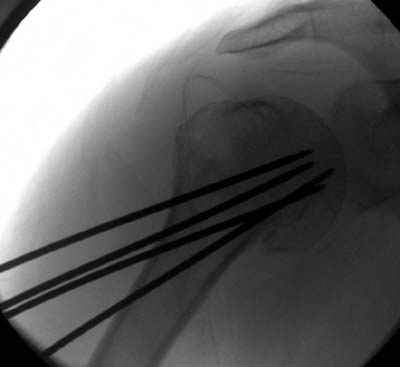

Здесь случай перелома-вывиха плеча, больному 56 лет, после "дважды" закрытой неудачной репозиции, опять же ургентно взяли в операционную, после полного общего обезболивания попытались сделать репозицию, и фиксацию провели спицами.

Больной находился в повязке, примерно напоминяющей косыночную, рекомендованы движения в локтевом суставе и маятниковые движения в плече, спицы удалены в три недели (были случаи миграции)

Клинические снимки - 3 недели после операции

Посылаю послеоперационные Рг граммы.